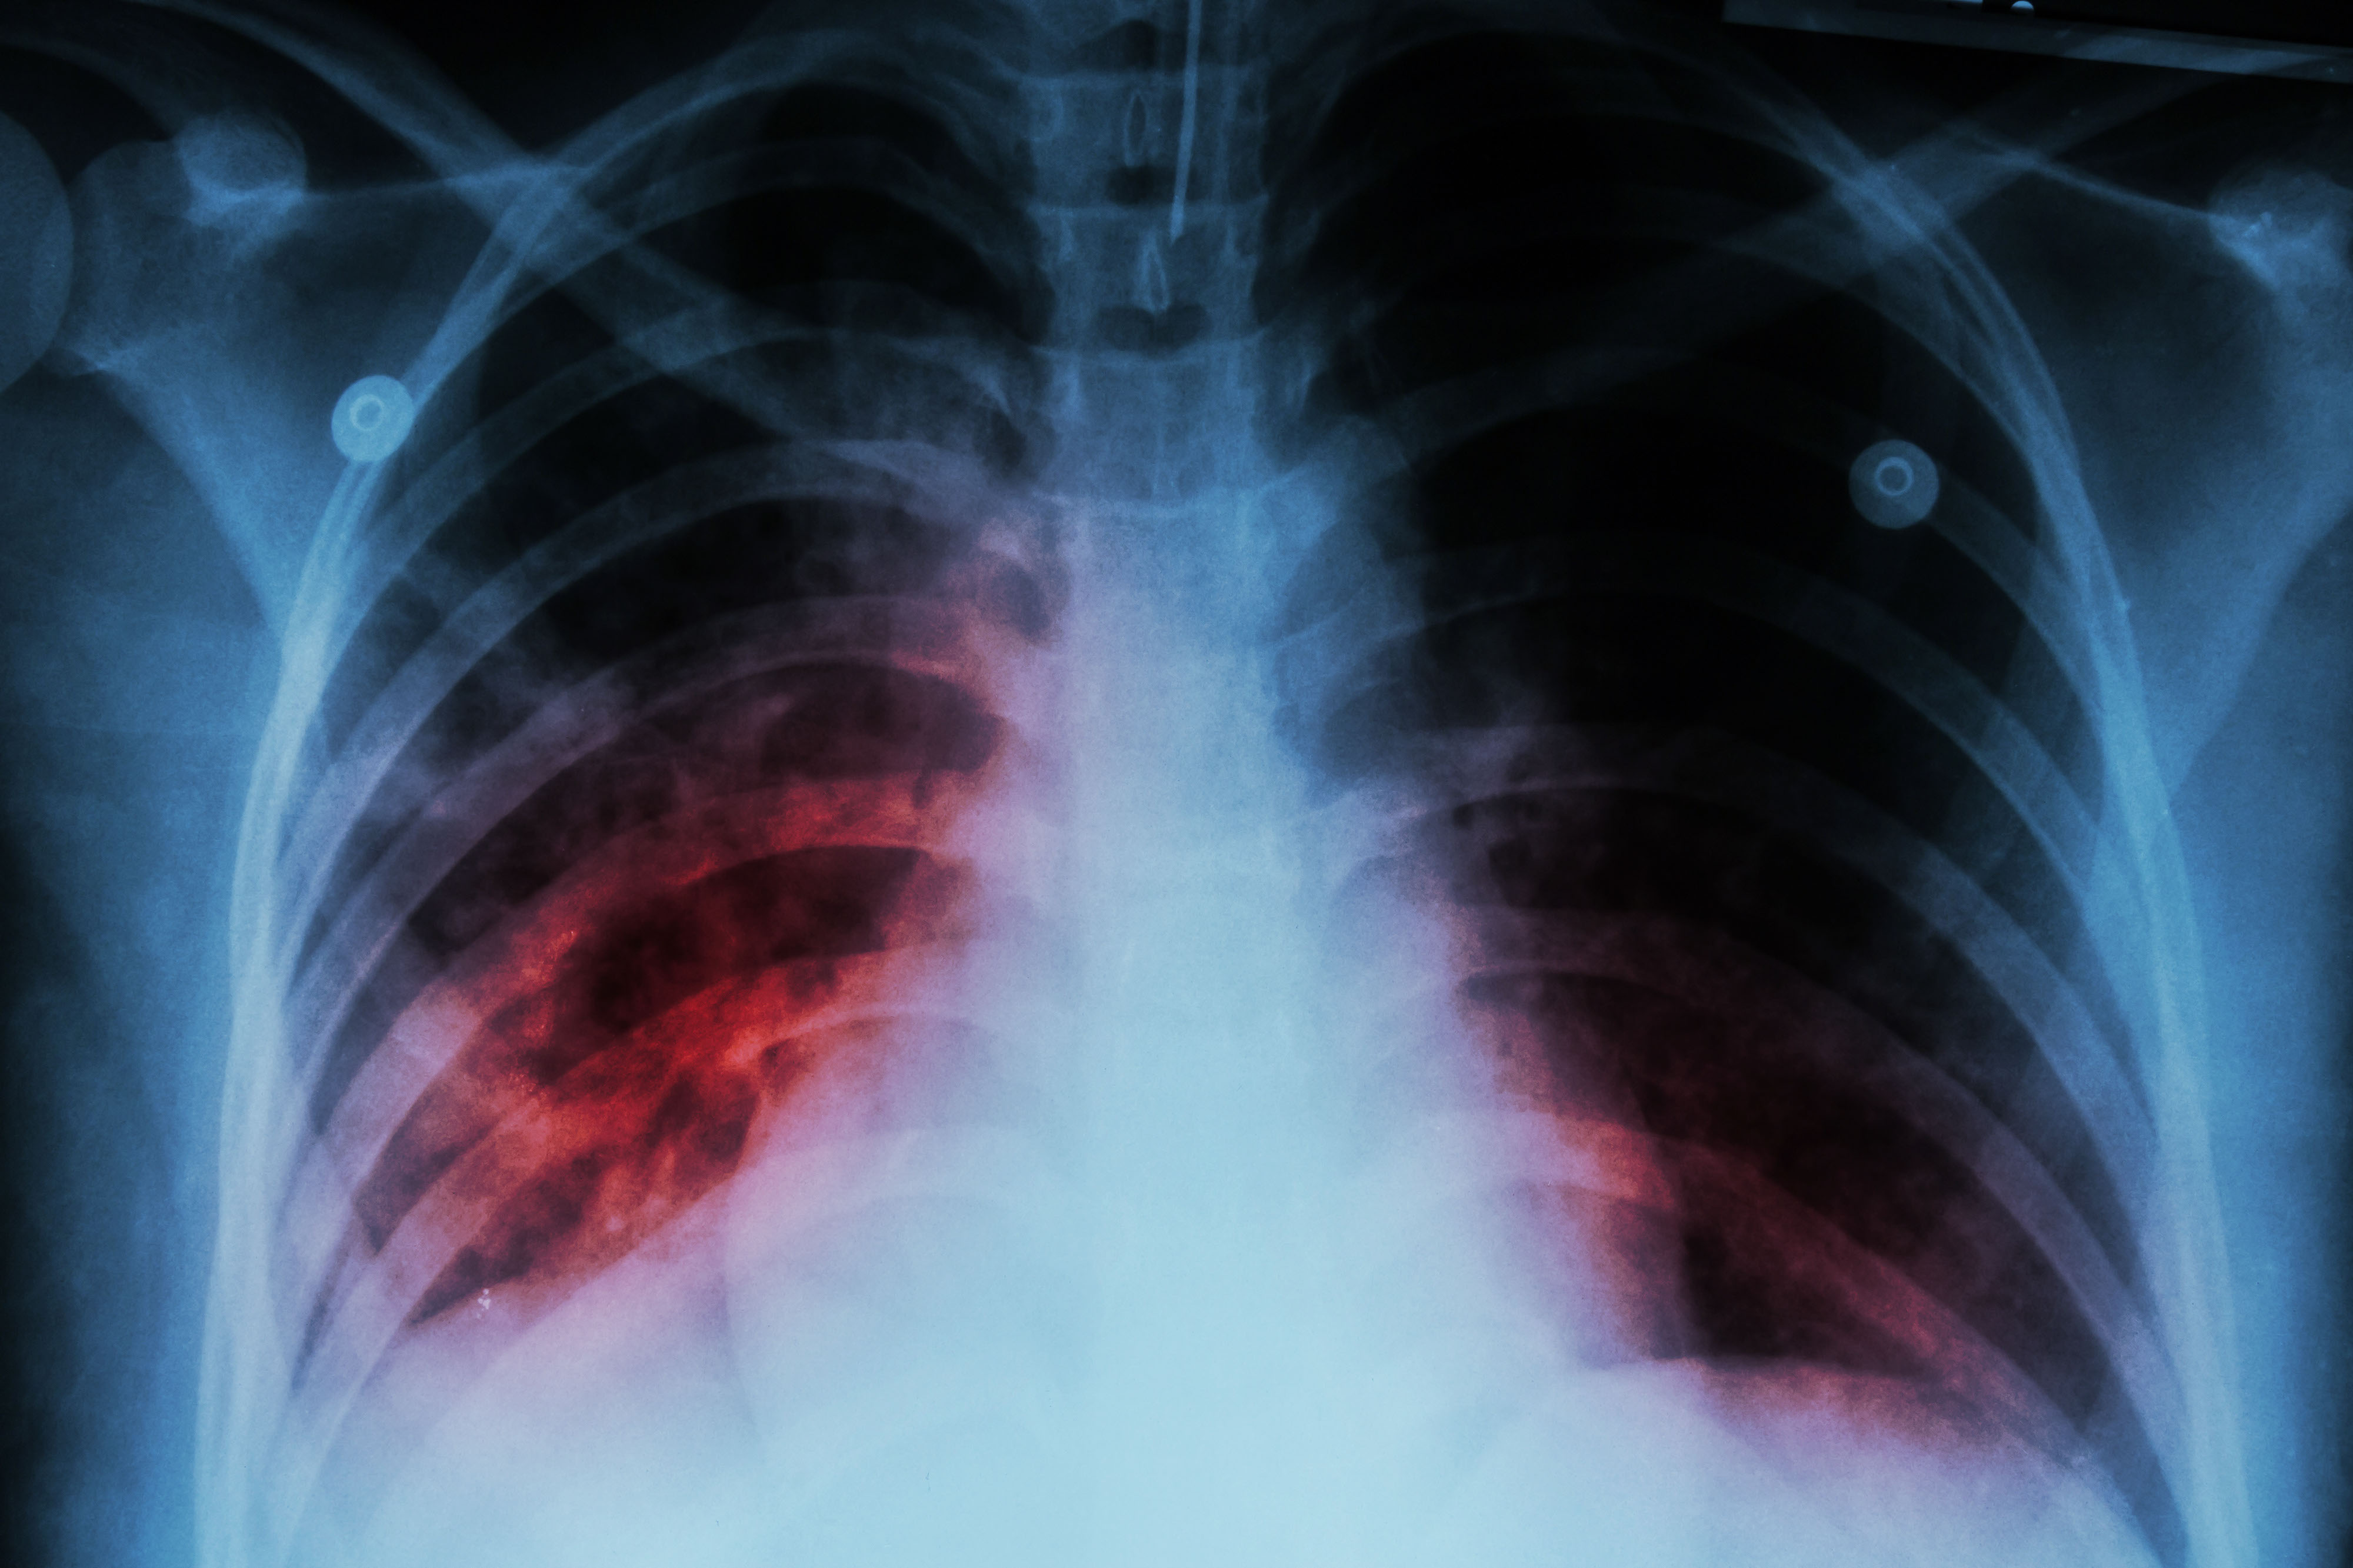

Clinical Phenotypes by Risk Category

Understanding how PE presents across the risk spectrum helps tailor both suspicion and urgency.

Massive (high-risk) PE:

- Features: Hypotension (SBP <90 mmHg for >15 min), shock, or cardiac arrest.

- Presentation: Pale, diaphoretic, tachycardic, hypotensive, with distended neck veins. Often the patient collapses abruptly (syncope, PEA arrest).

Mortality is high if reperfusion is delayed [1].

Submassive (intermediate-risk) PE:

- Features: Normotensive but evidence of RV dysfunction (echo RV dilation, McConnell sign) and/or biomarker elevation (troponin, BNP).

- Presentation: Dyspnea, tachypnea, mild hypoxemia, maybe borderline blood pressure. These patients can look stable but deteriorate rapidly if not closely monitored [4,7].